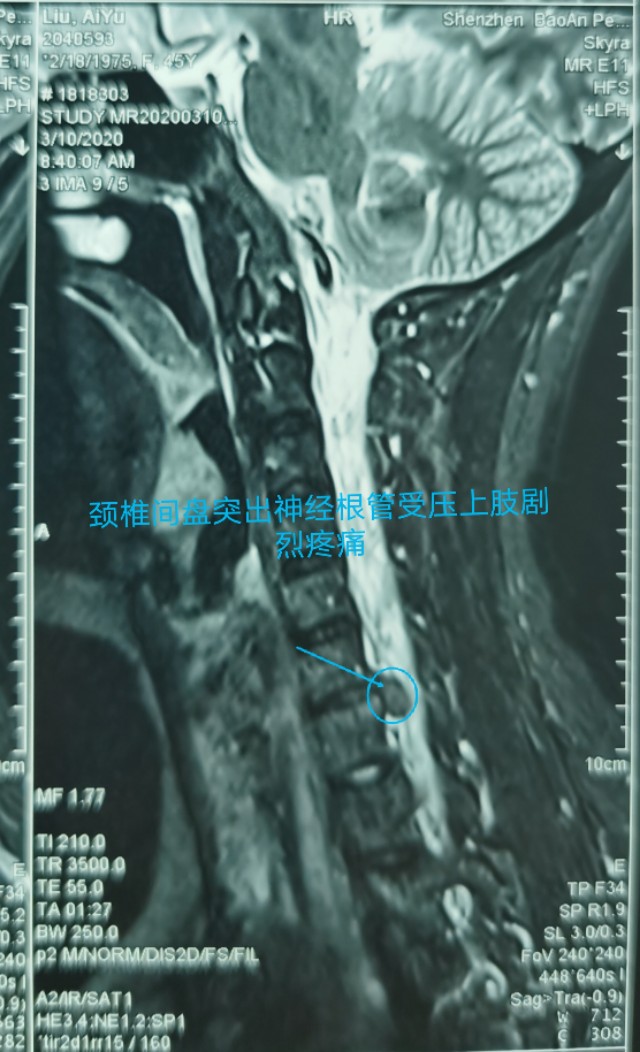

中年人疫情期居家长期卧床及长期看电脑手机,颈椎病复发今天显微镜下微创治疗,颈6-7巨大椎间盘突出.压迫神经根管,伴左上肢剧烈放射痛,显微镜下微创颈椎间盘突出治疗,用时半个小时,近零出血,取出压迫神经4块髓核,切除后纵韧带,减压至脊髓表面,脊髓恢复正常搏动,神经监护神经功能恢复好